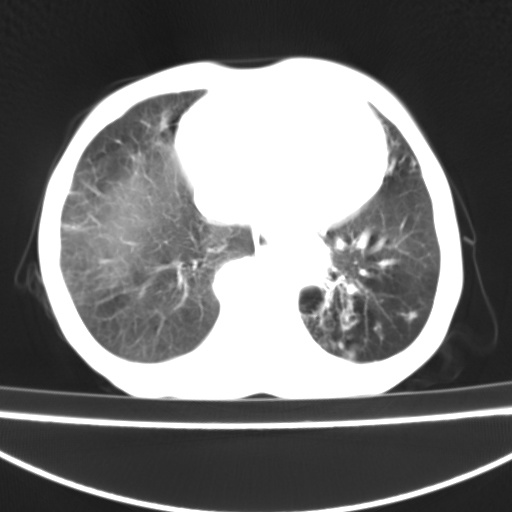

患者 女 67岁,反复咳嗽咳痰2年,加重伴喘及双下肢浮肿1月

诸大血管及f肺门血管增粗迂曲.左下肺多发薄壁空腔影.部分非也透亮度增高.薄曾扫描可区分肺气肿类型.考虑1.慢性支气管炎 2.左下肺支气管扩张 3.肺气肿 4 肺动脉高压5.是否有先心病病史

考虑1.慢性支气管炎 2.左下肺支气管扩张 3.肺气肿 4 肺动脉高压

慢支炎、肺气肿、双肺感染、左下囊状支扩。

慢支、肺气肿、肺动脉高压;左下肺囊状支扩并粘液栓形成。